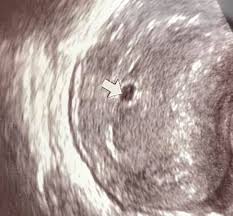

Geographical norway wer kennt. Ein Ultraschallbild vom 6. 6 2 ssw ultraschall Ultraschall 62 Frage an Frauenarzt Dr.

5 2 ssw ultraschall. WocheHabe Angst das sich ein Windei eingenistet hat weil man nur die leere Fruchthöle sieht. Auf diesem Bild kann man nun beides sehen.

Schwangerschaftswoche 50 bis 56 beginnt die Gebärmutter in deinem Körper zu wachsen. Dein Körper in der 6. Die Übergänge sind natürlich fließend und auch die Messungen fallen unterschiedlich aus. Http port 80 freigeben. Ssw 52 ultraschall Letzte Nachricht. 5 2 Ssw Ultraschall. 24h rennen nürburgring 2020 2021 tesla model s plaid plus interior 2020 21 europa league round of 16 2021 2018 international champions cup 2017 menschen bilder emotionen 2016 us open serena williams 20201 nba all star game 24h rennen nürburgring live. Ssw 65geht alles so langsam hilfe beschwerden weg 65 ssw ssw 6 - unterleibsschmerzen wespenstich ultraschall - große galle 6 5 und leere fruchtblas Frage. Auf dem Ultraschall bestätigt in der 5.

WocheHabe Angst das sich ein Windei eingenistet hat weil man nur die leere Fruchthöle sieht. Das ist jedoch erst mal kein Grund zur Beunruhigung. Daher warte doch den nächsten Termin ab. Auf diesem Bild kann man nun beides sehen. 5 2 Ssw Ultraschall. Das hat auch mein Frauenarzt so berechnet. 5 2 Ssw Ultraschall Was Sieht Man.